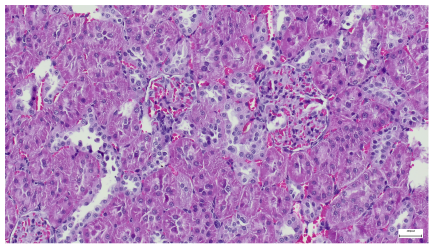

| 4.1. Hematoxylin and Eosin stain, 200× magnification. Normal aspect of the glomerulus, afferent arteriole, efferent arteriole, and normal renal tubules. Control group specimens. | 4.2. Hematoxylin and Eosin stain, 200× magnification. Normal aspect of the juxtaglomerular apparatus. Control group specimens. |